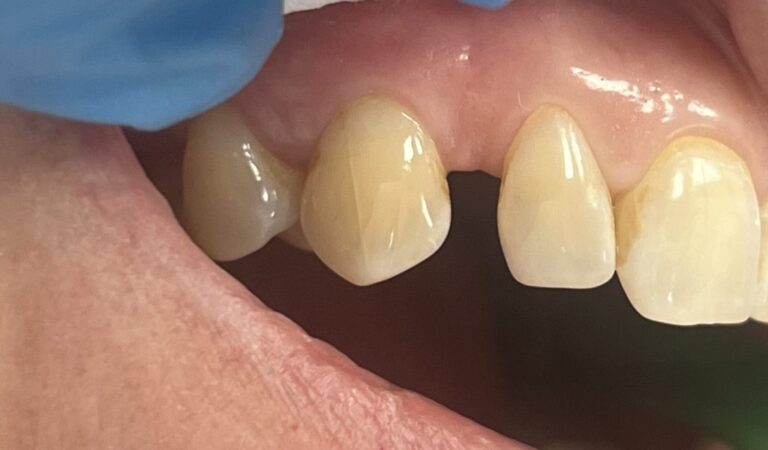

Czym jest elektrokoagulacja? Elektrokoagulacja to zabieg polegający na kontrolowanym wykorzystaniu prądu elektrycznego w celu zamknięcia naczyń krwionośnych oraz usunięcia zmienionych tkanek. W stomatologii metoda ta znajduje zastosowanie przede wszystkim w chirurgii i periodontologii. Stomatolog w nowoczesnej klinika stomatologiczna Kraków wykorzystuje…